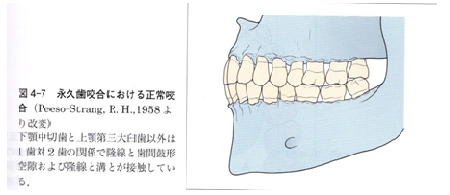

個性正常咬合とはどの様な咬合なのでしょうか?

ここは抜歯、非抜歯を選択するポイントとなるところです。

図を使って説明していきます。

ここはキー・ポイントとなるところですが、個性正常咬合では少なくとも28本の歯が図の様に咬合している状態を目標としているのです。

また、当然この図の様な歯列の不正は改善されている事は、言うまでもありません。